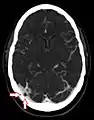

CT angiography showing an arachnoid granulation in the right transverse sinus

Non-contrast CT scan of the head showing an arachnoid granulation